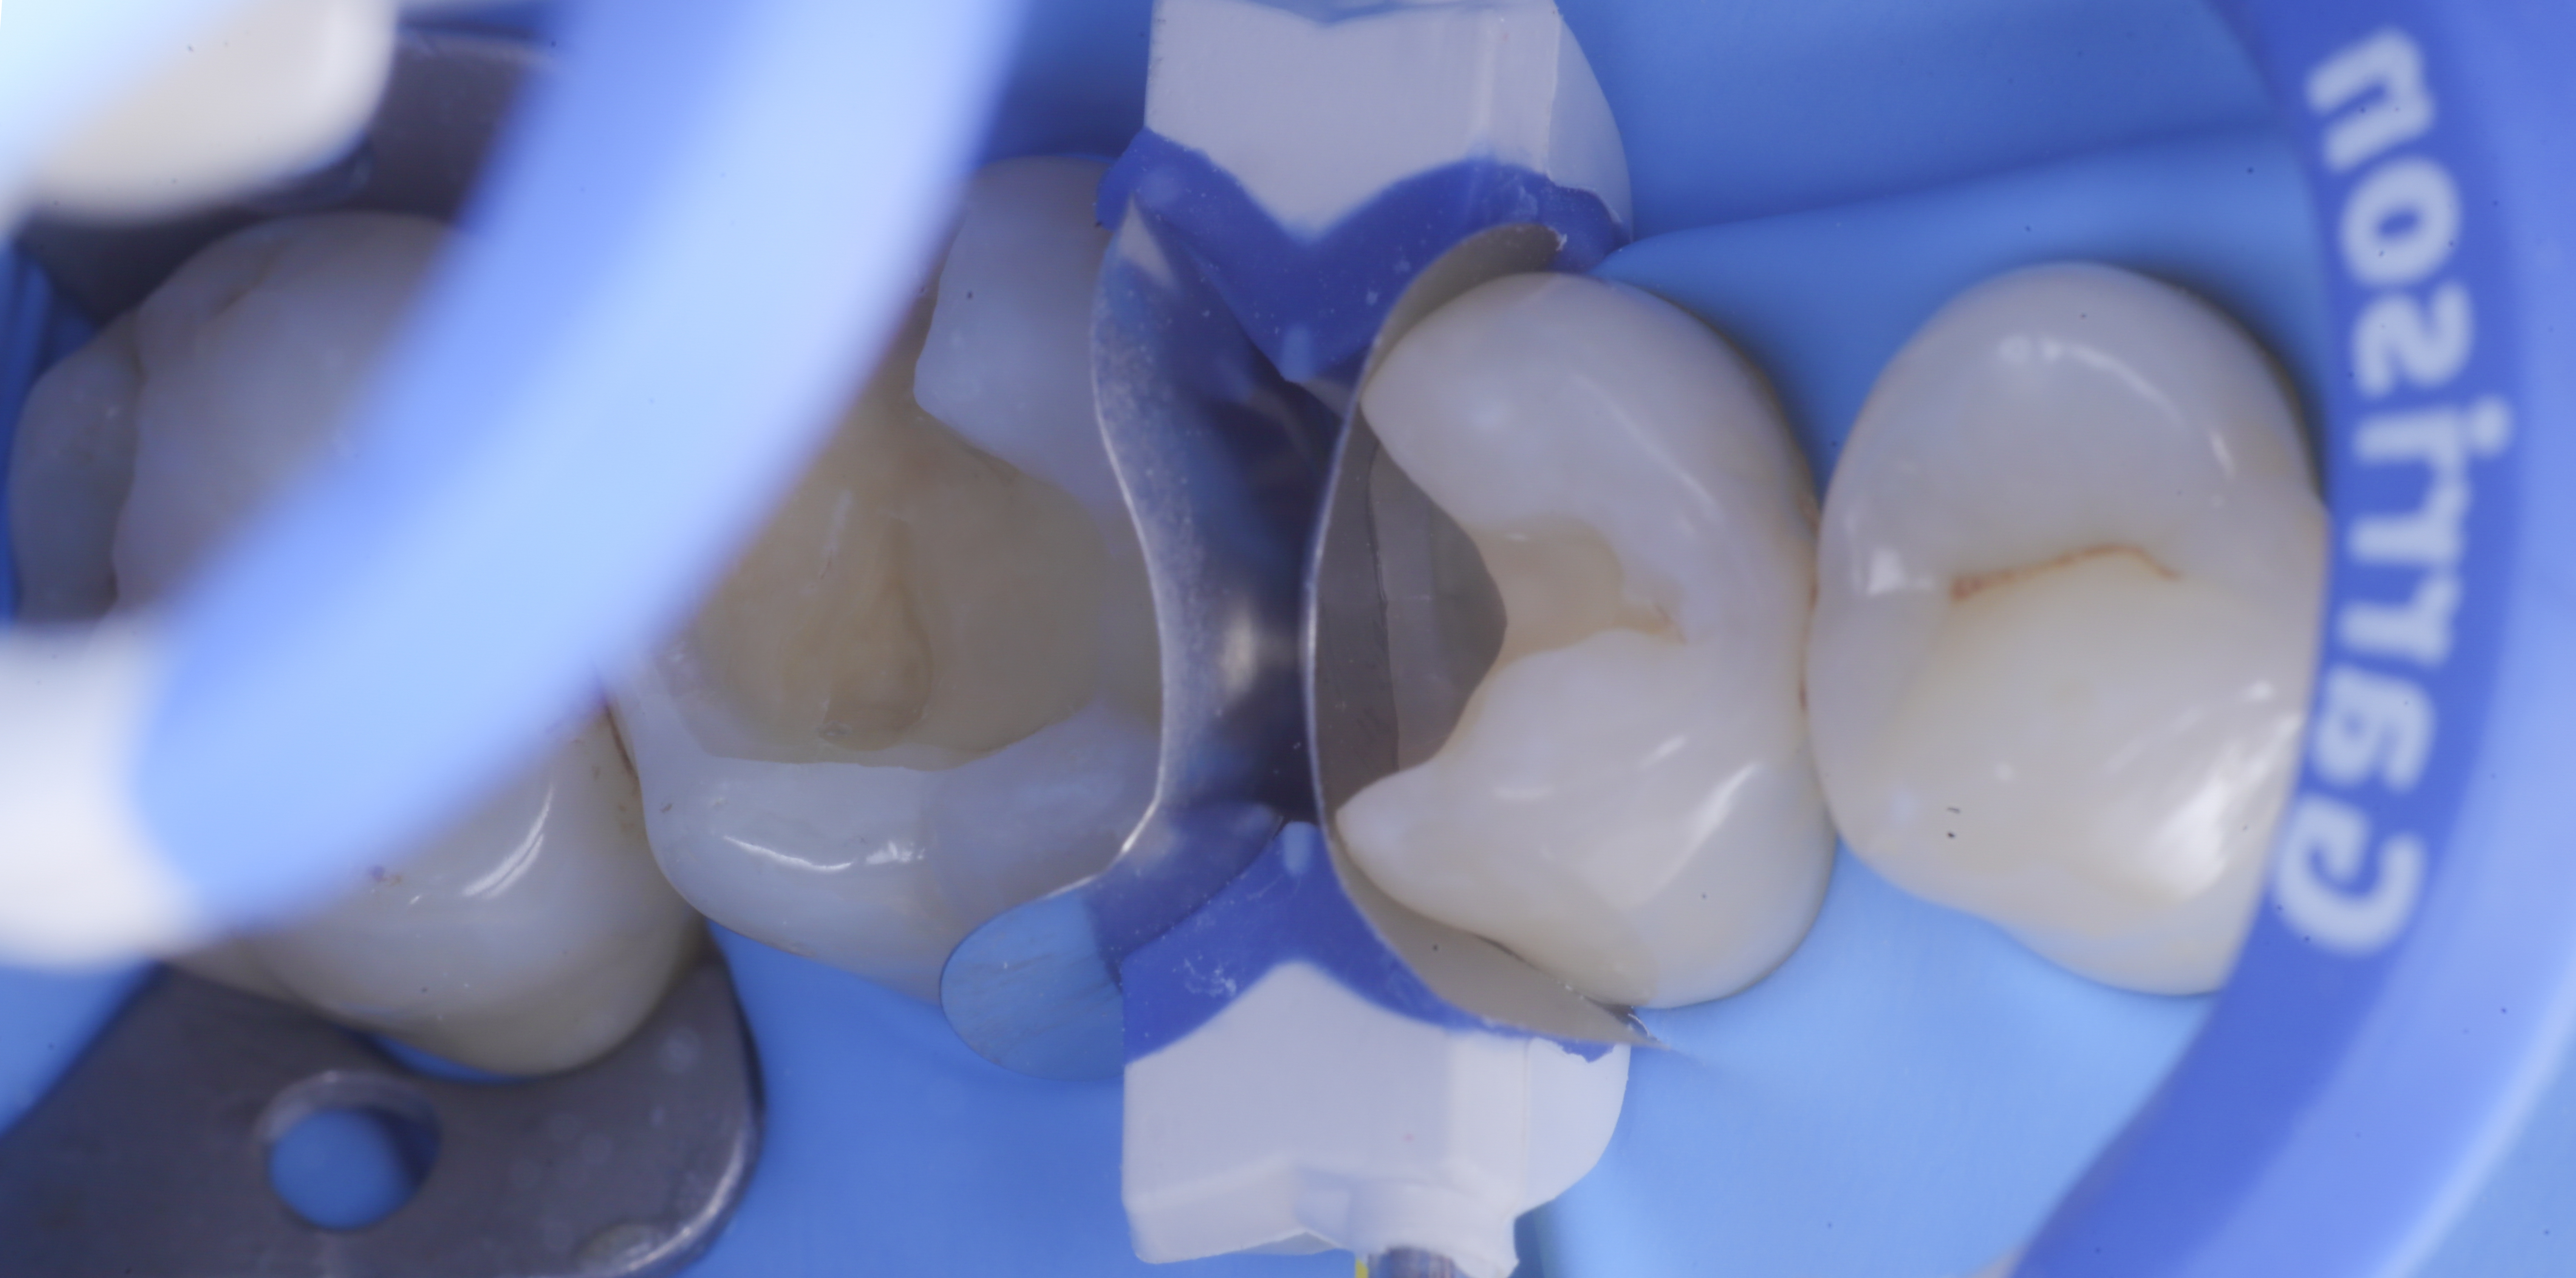

foto 3 Aspetto vestibolare della cavità ultimate

foto 4 Aspetto della chiusura cervicale e sulle pareti assiali dato dalla prima matrice